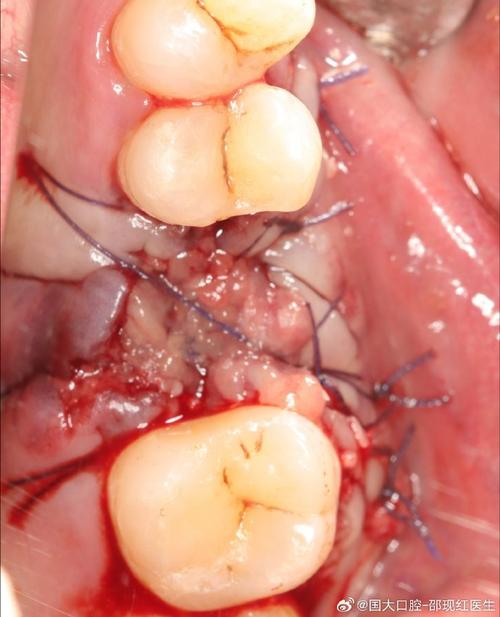

- 手术治疗:

- 翻瓣清创:翻开牙龈,彻底清洁种植体表面。

- 骨增量:骨缺损严重时植入骨粉引导再生。